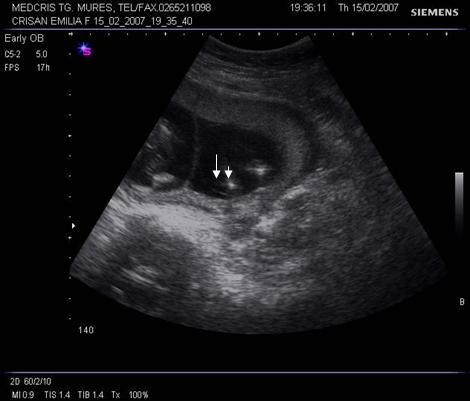

Fig nr 38. Sarcina biamniotica bichoriala 6 sapt . dupa

inseminare intrauterina cu stimulare ovariana, cele doua sageti marcheaza zona

de nidatie, respectiv placentatie, iar sacii amniotici sunt evident separati,

cu cate un embrion